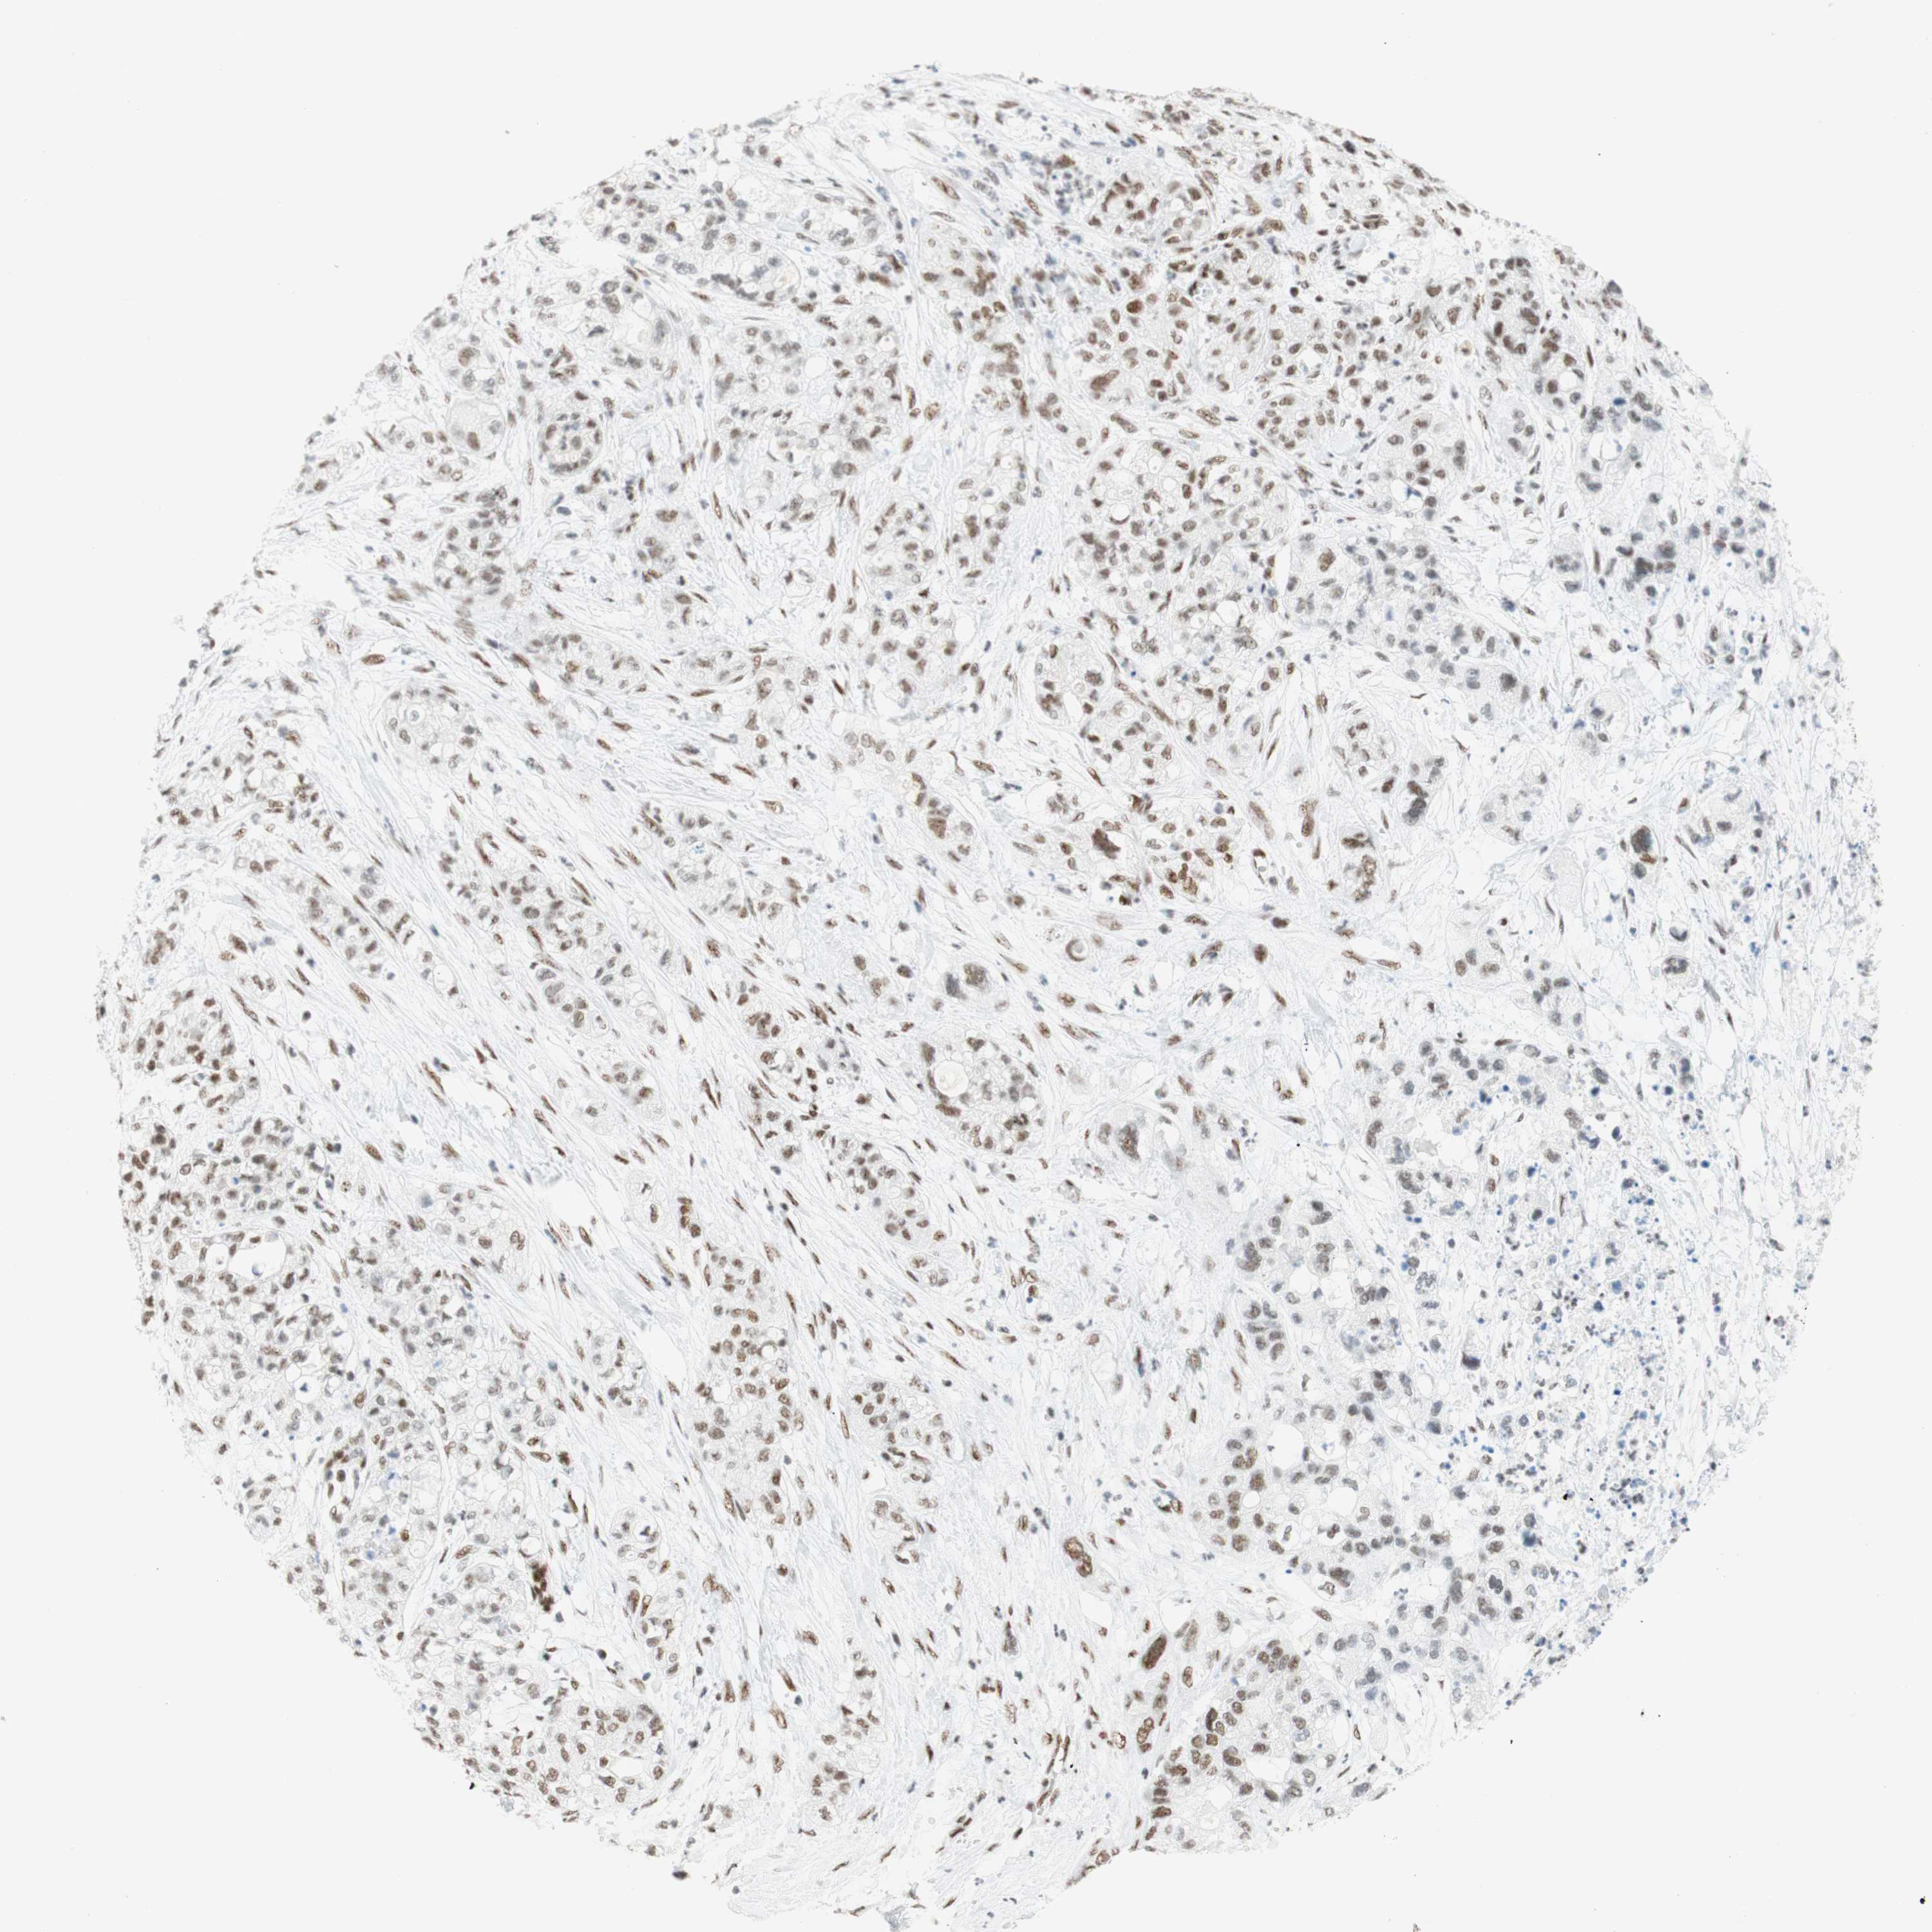

PANCREATIC CANCER - Protein expressioni

A mouse-over function shows sample information and annotation data. Click on an image to view it in a full screen mode. Samples can be filtered based on level of antibody staining by selecting one or several of the following categories: high, medium, low and not detected. The assay and annotation is described here.

Note that samples used for immunohistochemistry by the Human Protein Atlas do not correspond to samples in the TCGA dataset.

Antibody stainingi

Antibody staining in the annotated cell types in the current human tissue is reported as not detected, low, medium, or high, based on conventional immunohistochemistry profiling in selected tissues. This score is based on the combination of the staining intensity and fraction of stained cells.

Each image is clickable and will lead to virtual microscopy that enables deeper exploration of all samples and also displays staining intensity scores, fraction scores and subcellular localization as well as patient and tissue information for each sample.

Antibody CAB012478

Staining

High

Medium

Low

Not detected

Intensity

Strong

Moderate

Weak

Negative

Quantity

>75%

75%-25%

<25%

None

Location

Nuclear

Cytoplasmic/membranous

Cytoplasmic/membranous,nuclear

Adenocarcinoma, NOS

Adenocarcinoma, metastatic, NOS